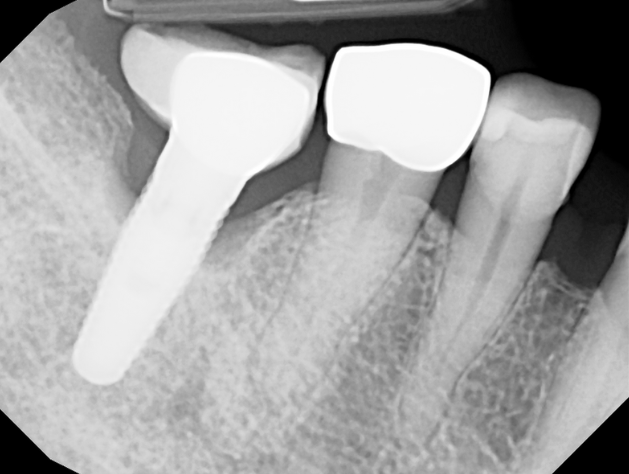

The LAPIP protocol offers a minimally invasive, laser-based method for treating peri-implantitis—the inflammation and bone loss that threatens the stability of dental implants. Using the same PerioLase® MVP-7™ technology as LANAP, LAPIP precisely targets infected tissue and harmful bacteria surrounding the implant while protecting healthy gum and bone. This allows the body to naturally rebuild lost support and helps save implants that would otherwise be at risk of failure. With no cutting or sutures required, LAPIP provides a gentle, highly effective alternative to traditional peri-implant surgery.

LAPIP™ (Laser-Assisted Peri-Implant Procedure) is a minimally invasive laser treatment designed to save ailing or failing dental implants caused by peri-implantitis. Using the PerioLase® MVP-7™ Nd:YAG laser, the protocol targets inflamed, infected tissue and titanium corrosion contaminants while preserving healthy gums and bone. This tissue-sparing approach promotes bone regeneration around the implant and offers a more comfortable treatment with less bleeding, swelling, and downtime than traditional surgery.

Removing and replacing a failing implant can require multiple surgical steps, bone grafting, and several months of healing, which significantly increases both time and cost.

LANAP and LAPIP have transformed how professionals treat gum disease and peri-implantitis. Instead of removing tissue, the protocols support natural healing by creating an environment where gums can reattach and bone can regrow. LANAP helps save natural teeth suffering from periodontal disease, while LAPIP can rescue implants that might otherwise fail—offering patients a predictable, minimally invasive alternative to traditional surgery.